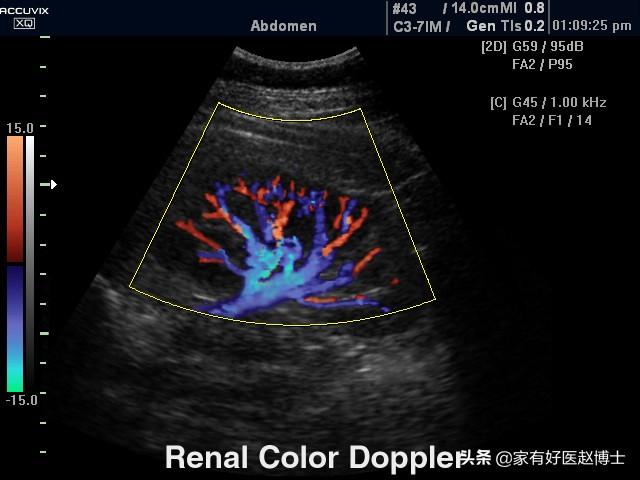

échographie rénale

L'échographie des artères rénales est également connue sous le nom d'imagerie de flux par échographie Doppler couleur, qui évalue l'indice de résistance au flux sanguin dans les artères rénales. Il a été démontré que les lésions rénales dues à l'hypertension sont les premières à provoquer une augmentation de la résistance au flux sanguin dans les artères interlobaires du rein, et donc de l'indice de résistance au flux sanguin dans les artères rénales.L'indice de résistance au flux sanguin des artères interlobaires rénales évalué par échographie de l'artère rénale peut également déterminer les lésions rénales hypertendues précoces。